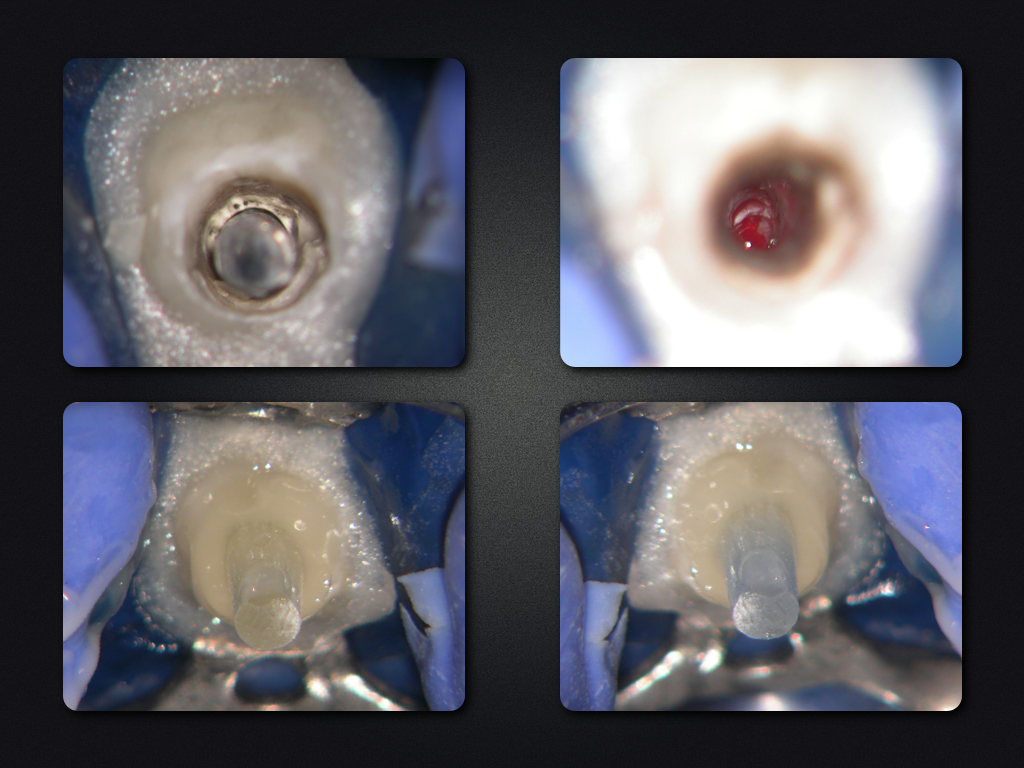

Und es heilt doch!